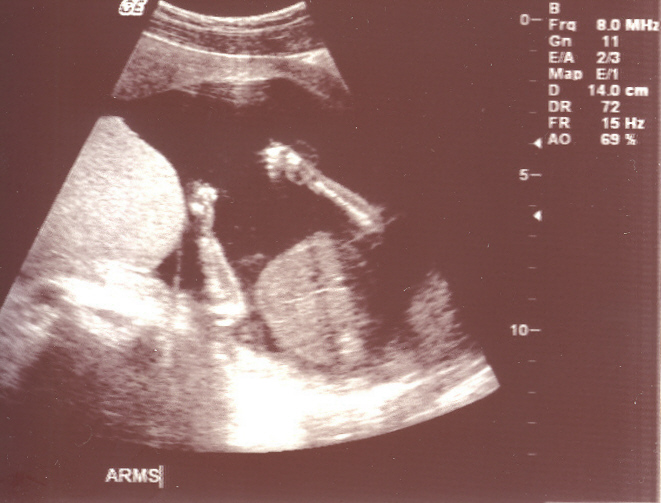

Our Tiny Baby